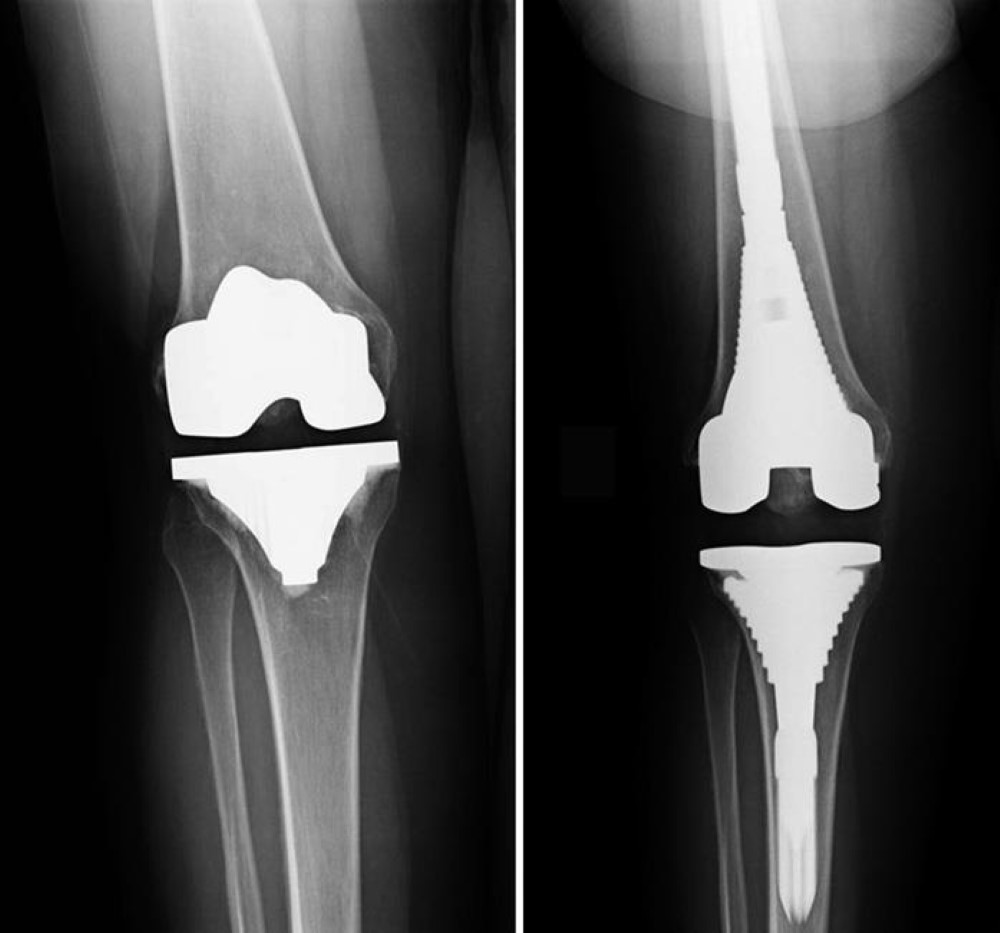

Revision Knee Replacement

Revision Knee Replacement means that part or all of your previous knee replacement needs to be revised. This operation varies from very minor adjustments to massive operations replacing significant amounts of bone. The typical knee replacement replaces the ends of the femur (thigh bone) and tibia (shin bone) with plastic inserted between them and usually the patella (knee cap).

Each knee is individual and knee replacements take this into account by having different sizes for your knee. If there is more than the usual amount of bone loss sometimes extra pieces of metal or bone are added.